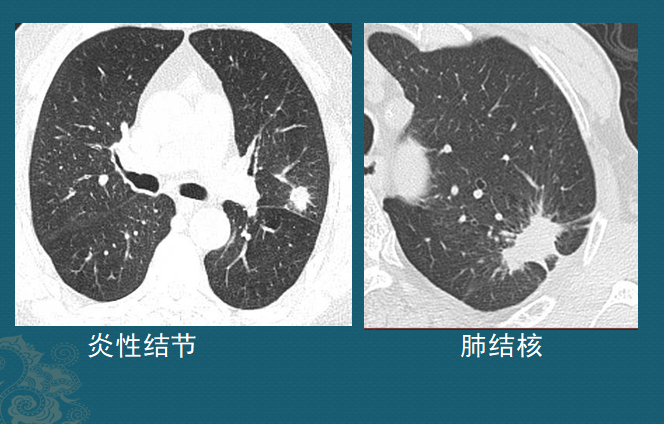

肺结节是怎么长出来的?医生用ct片详解,有2种可能是肺癌

肺磨玻璃结节的ct诊断